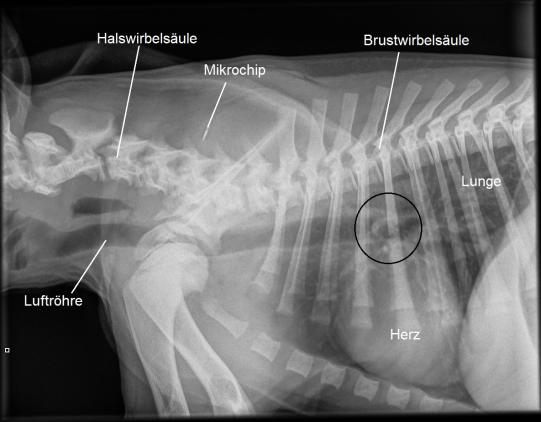

Der quirlige Welpe ist schwierig zu untersuchen. Da der Husten sehr stark ist und akut begonnen hat, scheint es möglich, dass Migo eine Verletzung der Atemwege aufweist oder gar einen Fremdkörper eingeatmet hat. Zwar findet sich auf einer Röntgenaufnahme des Brustkorbs ein verdächtiger Bereich in der Gegend der Luftröhrenaufzweigung (schwarzer Kreis); eine definitive Diagnose ist so aber nicht möglich.